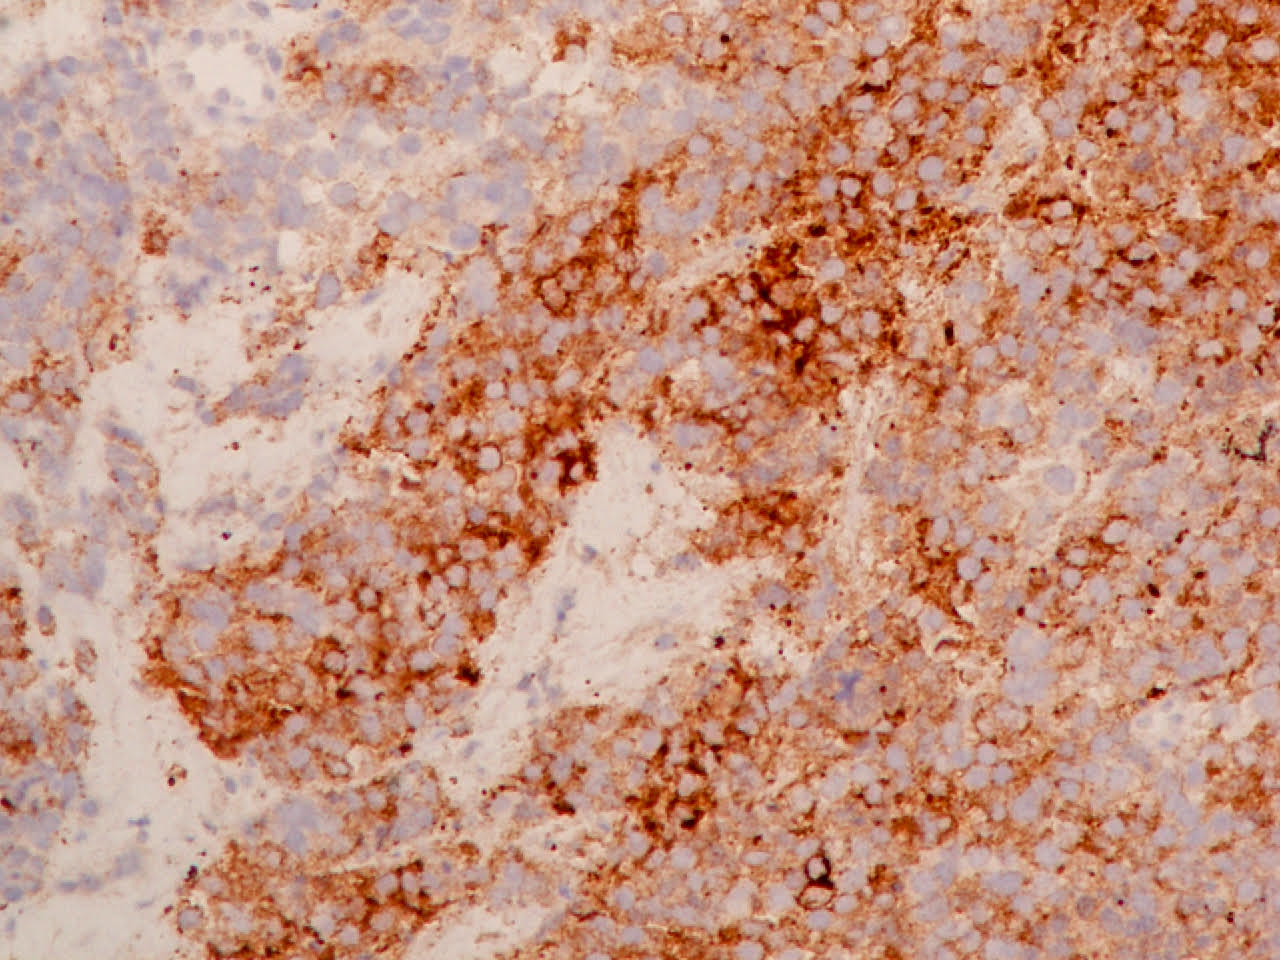

Microscopic (histologic) images

Contributed by Ioanna Abba Nteka, M.D., Aggeliki Cheva, M.D., Ph.D., Antonia Loukousia, M.D., Roseann Wu, M.D., M.P.H. and Kyriakos Chatzopoulos, M.D., Ph.D.

Positive stains

- Neuroendocrine markers, usually at least 2 focal to diffuse (chromogranin, synaptophysin, CD56), caution if CD56 is the only neuroendocrine marker expressed

- ISNM1: panneuroendocrine marker; nuclear positivity in 91.3% of large cell neuroendocrine carcinomas (Am J Surg Pathol 2017;41:1561)

- ASCL1: nuclear expression in 72.7%; neurogenic / neuroendocrine transcription factor (Hum Pathol 2016;48:142)